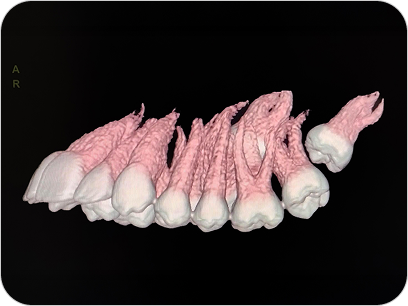

Dental Scan (Tomografía 3D Dental)

El Dental Scan o Tomografía Computada de Haz Cónico (CBCT) es un estudio especializado que brinda imágenes tridimensionales de alta resolución del sistema dentomaxilofacial. Es fundamental en odontología avanzada, permitiendo planificaciones precisas y diagnósticos más seguros.

La tomografía dental (CBCT) es un estudio esencial en odontología avanzada, que permite ver el maxilar, mandíbula y piezas dentales en 3D para diagnósticos y tratamientos más seguros.

UTILIDAD

- Planificación de implantes dentales.

- Evaluación de muelas del juicio y piezas retenidas.

Diagnóstico de quistes, lesiones óseas o problemas articulares.

VENTAJAS

- Imágenes 3D de alta resolución.

- Baja radiación.

- Ideal para odontología, ortodoncia y cirugía maxilofacial

¿PARA QUÉ SE UTILIZA?

- Planificación de implantes dentales con medición exacta del hueso.

- Evaluación de muelas del juicio o dientes incluidos.

- Estudio de quistes, tumores o lesiones óseas de mandíbula y maxilar.

- Diagnóstico de patología articular (ATM).

- Detección de fracturas, reabsorciones o infecciones profundas.

- Cirugías ortognáticas y procedimientos maxilofaciales complejos.

¿POR QUÉ ES UN ESTUDIO DESTACADO?

- Imágenes en 3D reales y de alta definición.

- Mucho más preciso que una radiografía panorámica tradicional.

- Estudio rápido, cómodo y con baja dosis de radiación.

Dental Scan (Tomografía 3D Dental)

El Dental Scan o Tomografía Computada de Haz Cónico (CBCT) es un estudio especializado que brinda imágenes tridimensionales de alta resolución del sistema dentomaxilofacial. Es fundamental en odontología avanzada, permitiendo planificaciones precisas y diagnósticos más seguros.

La tomografía dental (CBCT) es un estudio esencial en odontología avanzada, que permite ver el maxilar, mandíbula y piezas dentales en 3D para diagnósticos y tratamientos más seguros.

UTILIDAD

- Planificación de implantes dentales.

- Evaluación de muelas del juicio y piezas retenidas.

Diagnóstico de quistes, lesiones óseas o problemas articulares.

VENTAJAS

- Imágenes 3D de alta resolución.

- Baja radiación.

- Ideal para odontología, ortodoncia y cirugía maxilofacial

¿PARA QUÉ SE UTILIZA?

- Planificación de implantes dentales con medición exacta del hueso.

- Evaluación de muelas del juicio o dientes incluidos.

- Estudio de quistes, tumores o lesiones óseas de mandíbula y maxilar.

- Diagnóstico de patología articular (ATM).

- Detección de fracturas, reabsorciones o infecciones profundas.

- Cirugías ortognáticas y procedimientos maxilofaciales complejos.

¿POR QUÉ ES UN ESTUDIO DESTACADO?

- Imágenes en 3D reales y de alta definición.

- Mucho más preciso que una radiografía panorámica tradicional.

- Estudio rápido, cómodo y con baja dosis de radiación.